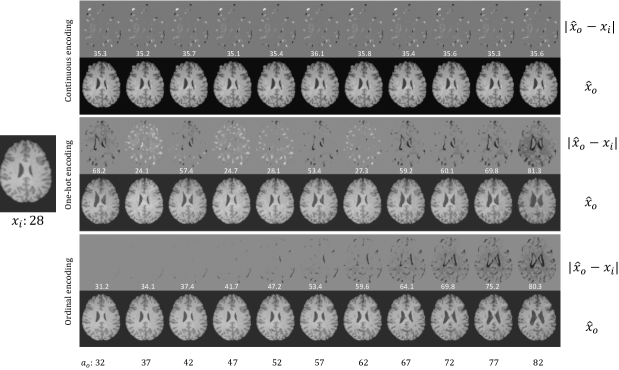

Fig. 12: Example results for continuous, one-hot and ordinal encoding on the Cam-CAN dataset for an image (𝐱isubscript𝐱𝑖\mathbf{x}_{i}) of a 28 year old subject. We synthesise aged images 𝐱^osubscript^𝐱𝑜\hat{\mathbf{x}}_{o} at different target ages aosubscript𝑎𝑜a_{o}. We also show the difference between 𝐱isubscript𝐱𝑖\mathbf{x}_{i} and 𝐱o^^subscript𝐱𝑜\hat{\mathbf{x}_{o}}, |𝐱^o𝐱𝐢|subscript^𝐱𝑜subscript𝐱𝐢|\hat{\mathbf{x}}_{o}-\mathbf{x_{i}}|, and report estimated age (white text overlaid at the bottom of each difference image). The proposed ordinal encoding shows consistent and progressive changes.

We investigate the effect of different embedding mechanisms. Our embedding mechanism is described in Section 3. We considered to encode age as a normalized continuous value (between 0 and 1) or using a one-hot vector, which was then concatenated with the latent vector at the bottleneck. The qualitative results are shown in Fig. 12. We can see that when age is represented as a normalized continuous value, this is ignored by the network, thus generating similar images regardless of changes in target age aosubscript𝑎𝑜a_{o}. When we use one-hot vectors to encode age, the network still generates realistic images, but the ageing progression is not consistent, i.e. synthetic brains appear to have ventricle enlarging or shrinking in random fashion across age. In contrast, with ordinal encoding, the model simulates the ageing process consistently. This observation is confirmed by the estimated ages of the output images by fpredsubscript𝑓𝑝𝑟𝑒𝑑f_{pred}.